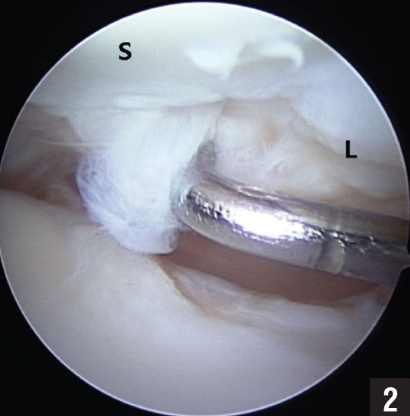

Voorbeelden van het geschuurde bandje tussen scaphoid (S) en lunatum (L) tijdens een kijkoperatie.